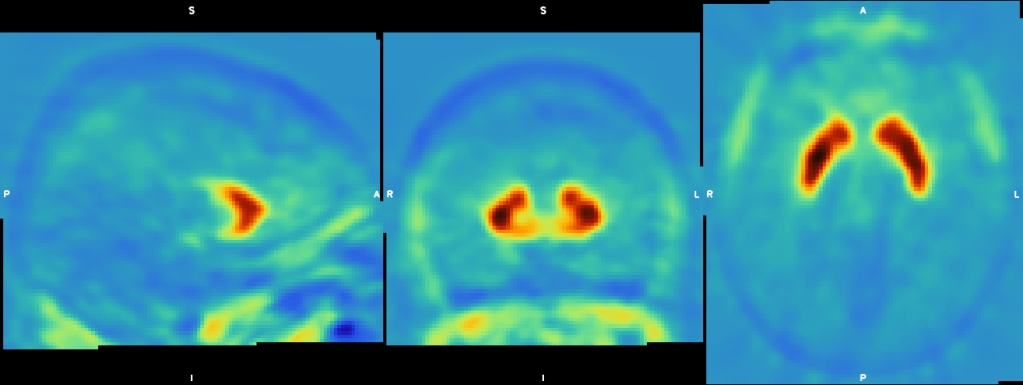

Giovanna liked the revised leaflet but had one more request – could the PET scan of the sagittal brain view (the lower PET scan illustration) show a red signal in the area of the striatum. Giovanna sent an example image (below) to show how this might look.

Gill revised the existing PET scan illustration to include the red signal, as shown in the header image to this blog post. This illustration was then added to the leaflet and also to the screen in the illustration of the radiographer’s office, before the updated leaflet (shown left) was sent on to Giovanna.